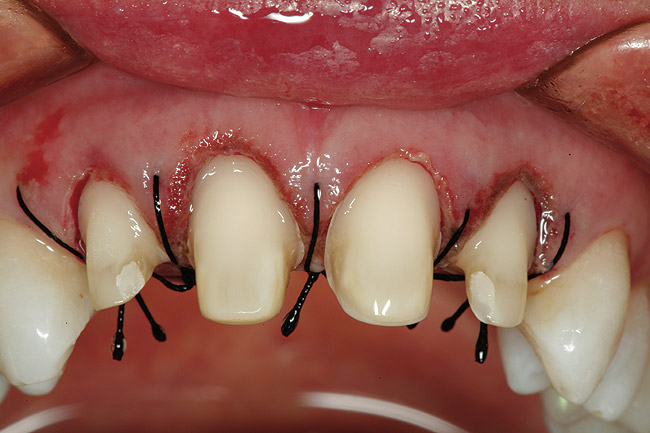

Figure 9  Facial view of tooth Nos. 7 through 10 after completion of the surgical phase of treatment.

Figure 9